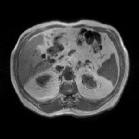

To better retain the deep features of an image and solve the sparsity problem of the end-to-end segmentation model, we propose a new deep convolutional network model for medical image pixel segmentation, called MC-Net. The core of this network model consists of four parts, namely, an encoder network, a multiple max-pooling integration module, a cross multiscale deconvolution decoder network and a pixel-level classification layer. In the network structure of the encoder, we use multiscale convolution instead of the traditional single-channel convolution. The multiple max-pooling integration module first integrates the output features of each submodule of the encoder network and reduces the number of parameters by convolution using a kernel size of 1. At the same time, each max-pooling layer (the pooling size of each layer is different) is spliced after each convolution to achieve the translation invariance of the feature maps of each submodule. We use the output feature maps from the multiple max-pooling integration module as the input of the decoder network; the multiscale convolution of each submodule in the decoder network is cross-fused with the feature maps generated by the corresponding multiscale convolution in the encoder network. Using the above feature map processing methods solves the sparsity problem after the max-pooling layer-generating matrix and enhances the robustness of the classification. We compare our proposed model with the well-known Fully Convolutional Networks for Semantic Segmentation (FCNs), DecovNet, PSPNet, U-net, SgeNet and other state-of-the-art segmentation networks such as HyperDenseNet, MS-Dual, Espnetv2, Denseaspp using one binary Kaggle 2018 data science bowl dataset and two multiclass dataset and obtain encouraging experimental results.